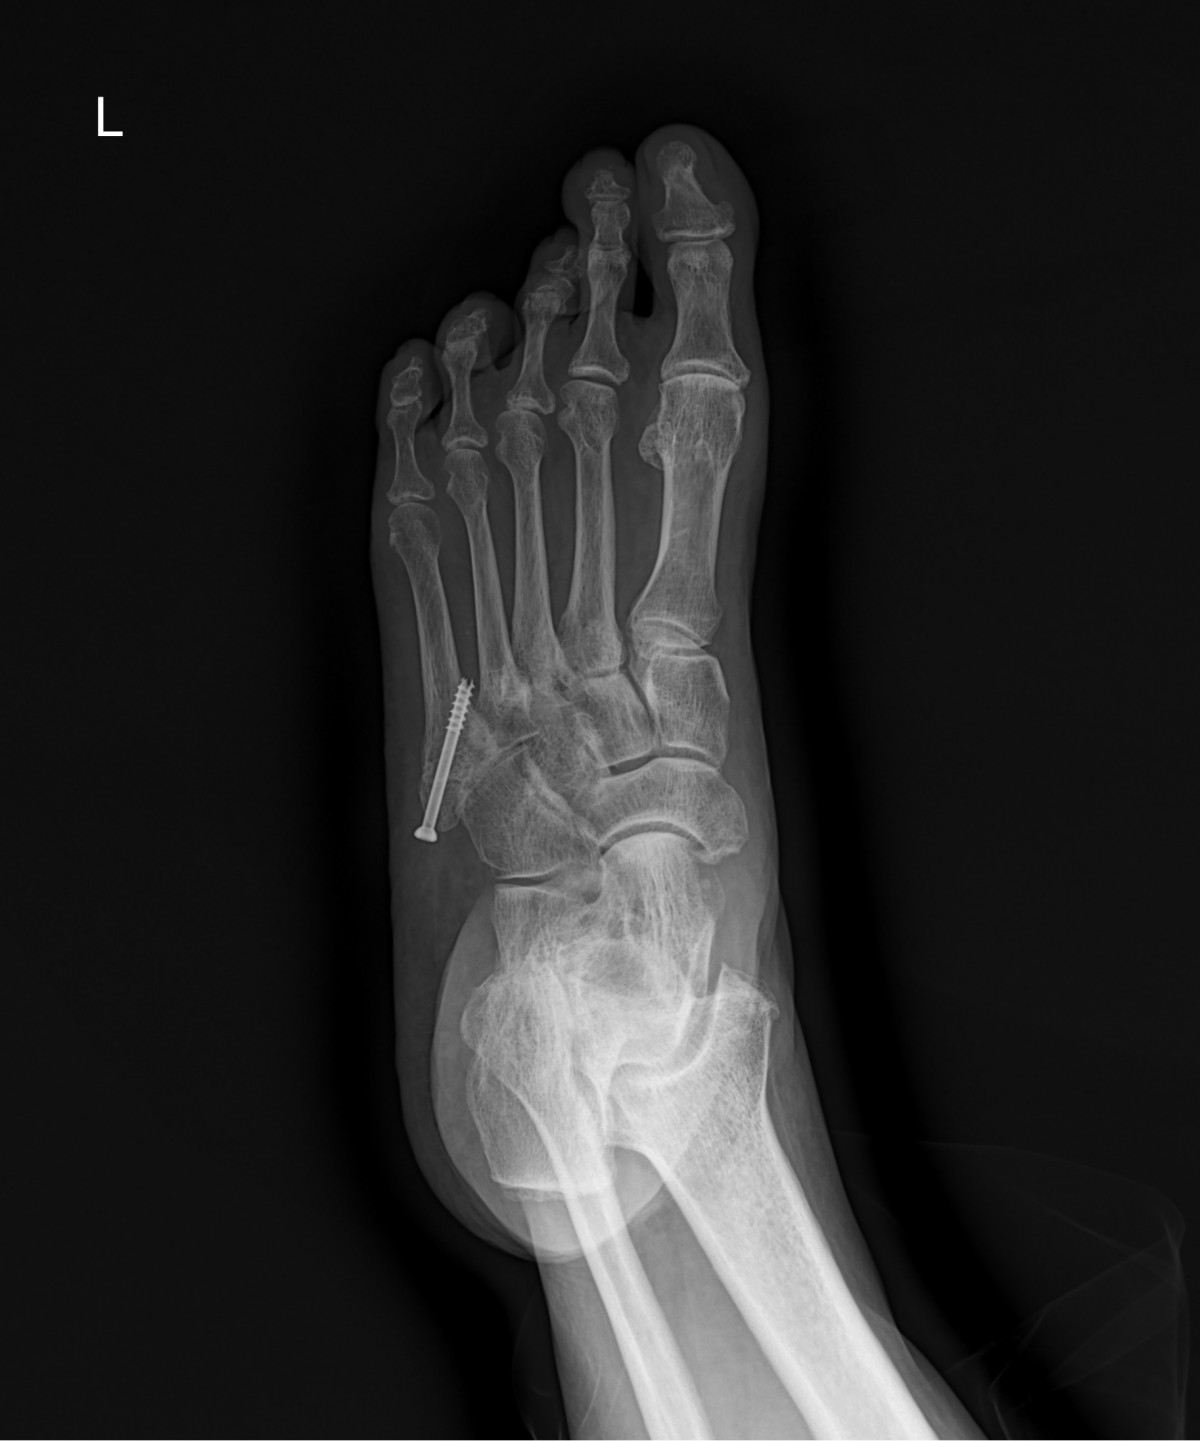

이재상원장님 발등 골절 수술 손선O 환자

dae765e4d9ac96aee867c9d6292d8784_1758003034_5114.jpg